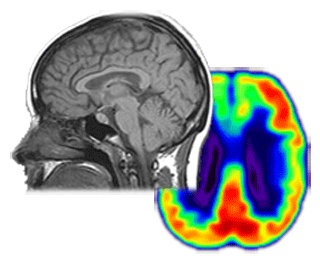

Dementia brain gif. Dementia is a broader term user to describe a range of progressive diseases that affect the brain. Theres currently no cure for the condition but medical experts. The effects of alzheimers disease on the brain often. Cause the symptoms of dementia.

Incidence of stroke white matter lesions and dementia also rise with age.